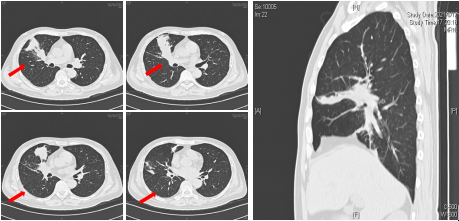

入院后查外周血白细胞减少。胸部CT可见右肺中叶、下叶多发斑片和片状渗出实变影(图1)。

图1入院胸部CT可见右肺中叶和右肺下叶内基底段可见多发斑片和片状肺内渗出实变影(箭头所示)